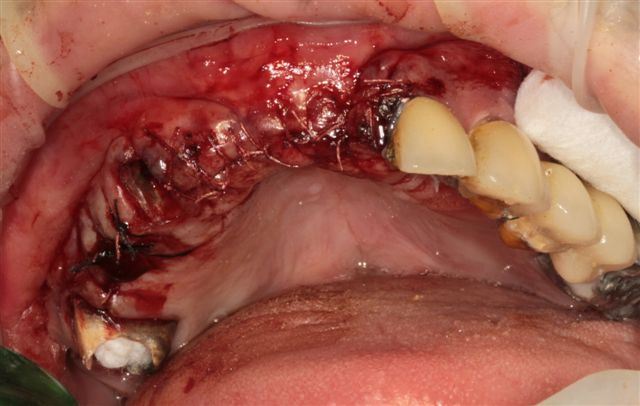

ثم جذبها حتى سقطت على الأرض ونزع اسنانها الأمامية وهي تصرخ ثم حملها إلى السيارة وقضى معها ليلته وقال لها أثناء الطريق إذا صدر عنك أي صوت سأنزع بقية أسنانك.

صعقنا من هول المفاجأة وتلمسنا أسنانا قبل أن نطلب منها أن ترينا فمها .

انتقلنا معها مباشرة لمفوضية الشرطة لطرح شكايتها وأخذنا رسالة من المفوضية لطبيب الاسنان لتحديد الضرر الجسدي أما النفسي فلا يمكن تحديده .